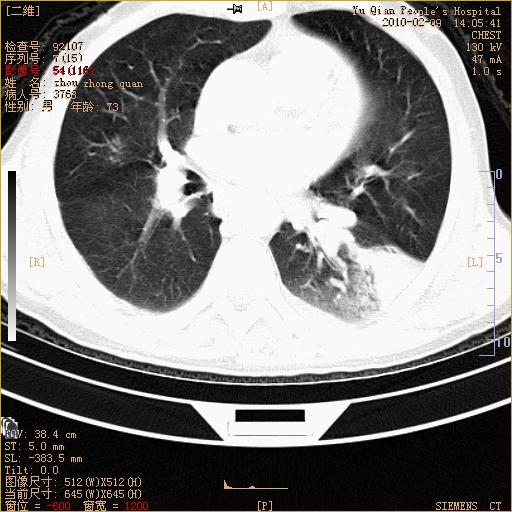

男性,73岁,咳嗽咳血数天,诊为肺ca伴左肺下叶后段阻塞性炎症、肺不张妥否?

右下肺有转移?

左下肺中央型肺癌伴结段形肺不张,左侧胸腔积液,纵隔内见部分增大淋巴结(反应性增生或转移)

左下基底干支气管明显变窄。

左肺下叶基底段支气管狭窄,左肺门增大,左肺下叶团片状病灶。中心型肺癌伴柱塞性炎症可能大,建议支气管镜检查。

左下肺中央型肺癌伴节段性肺不张,左侧胸腔积液,纵隔内见肿大淋巴结

左下基底段支气管变窄。建议进一步纤支镜检查。

1、左肺下叶后基地段肺癌伴阻塞性炎症,左下肺门淋巴结转移。2、左侧胸腔积液。